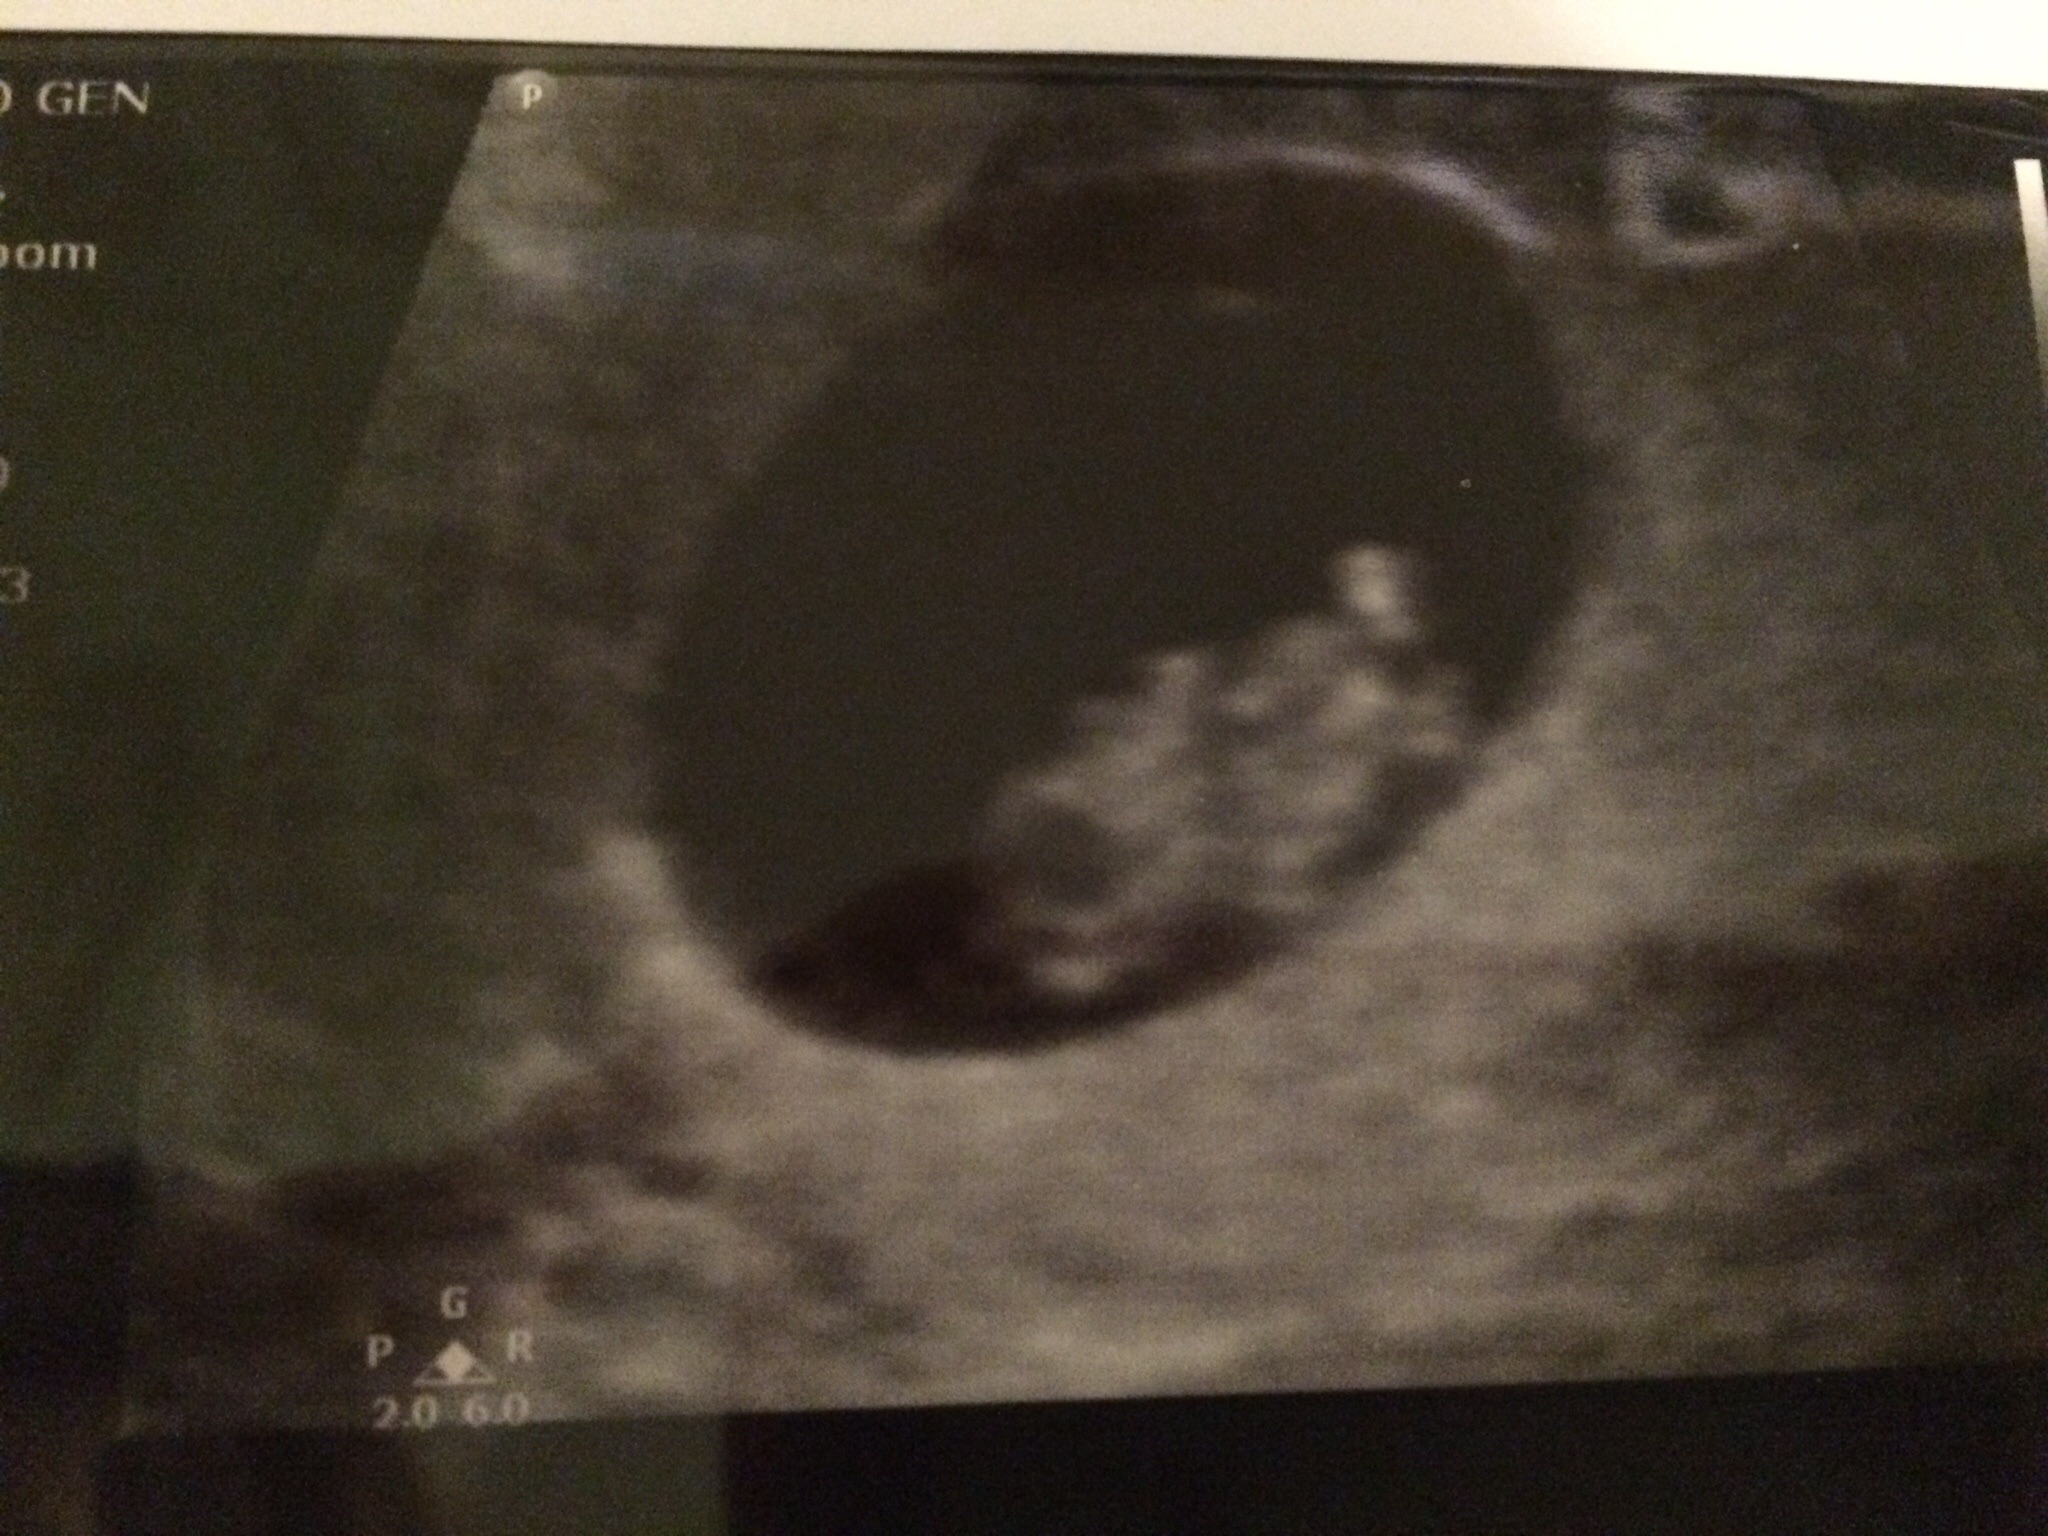

Could anyone have a look at my 8week 5day ultrasound done abdominal

Ramzi works for transvaginal U/S as far as I know (if it works at all).

I came across your post through a RAMZI google search. I know it's late but I would guess PINK!

According to Ramzi this would be a Girl! BUT his theory supposedly only works until week 8 ..... (6-8)

I guess BOY

It was a boy!

Dr. Ramzi himself has guessed wrong on several ultrasounds. This ultrasound was an abdominal one anyway and so it could not have been accurate on this person's pics.